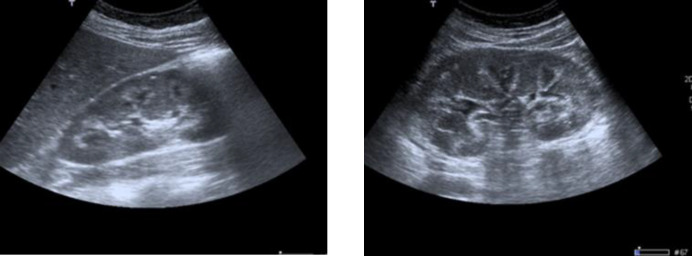

Background: Furosemide is a drug widely used for several medical conditions and could be used without medical prescription. Furosemide-related nephrocalcinosis can occur regardless of age, although the risk is higher in premature infants. The defining characteristic of nephrocalcinosis is generalized calcium deposition in the kidney. The most useful imaging studies for evaluation are ultrasonography and computed tomography (more effective in detecting calcification).

Case presentation: A 32-year-old woman with a history of depressive syndrome was admitted for evaluation of fortuitously discovered nephrocalcinosis and hypokalemia. The studies performed revealed the presence of a metabolic alkalosis with discrete hyperreninism/hyperaldosteronism but normal ratio, normotension and urinary study showed elevated sodium, chloride, potassium and calcium fluctuating in different determinations. Surreptitious diuretic intake was suspected and urine analysis revealed doses equivalent to 80-120 mg. The patient was advised to discontinue all diuretic treatment; she was adequately supplemented with potassium and she was followed-up in outpatient clinics. During the follow-up, clinical and analytical improvement was noted, which led to the discontinuation of supplementation.